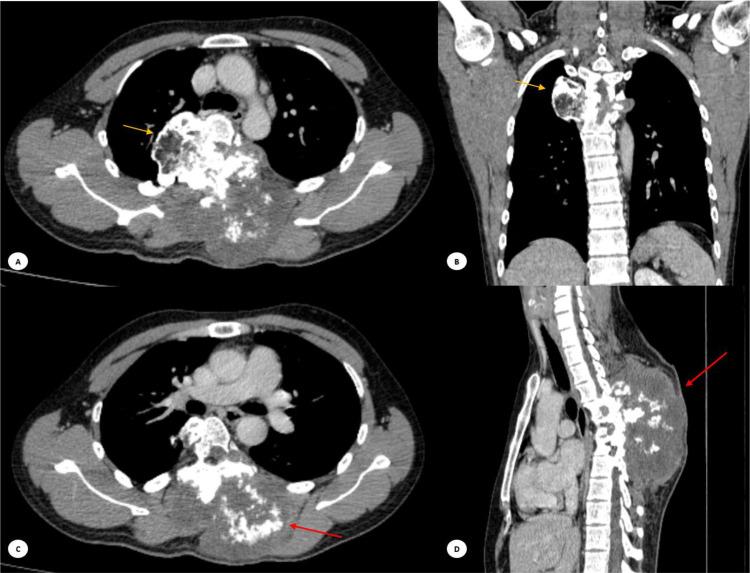

Chondrosarcomas are one of malignant tumors in which cartilaginous matrix is produced. It is divided into 2 groups including primary or secondary. Primary chondrosarcomas are the third most common primary malignant tumors of the bone. Chondrosarcoma represents 20%-27% of all primary malignant bone tumors. Primary spinal chondrosarcoma is exceedingly rare among spinal tumors. A 36-year-old man presented to hospital with the swelling on the back accompanied with pain. Swelling and pain have been felt for approximately 3 years. The symptoms gradually worsened. On thoracolumbal X-ray a lytic sclerotic expansile lesion on the right posterior aspect of thoracal T5-T6. MRI showed the mass infiltrated intradural and intramedullary, reaching up to the level of vertebrae T4-T5. This infiltration resulted in stenosis of the spinal canal, obliterating the ligamentum flavum, supraspinous ligament, and interspinous ligament. Chondrosarcomas are uncommon malignant bone tumours that form cartilage; they rarely involve the spine, while most of them occur in young men. The thoracic spine is most commonly involved, but there is usually a long history of pain and possible neurological symptoms. Imaging techniques, such as conventional examination, CT, and MRI, are very important for diagnosis and classification and show typical bone destruction with matrix mineralization. Imaging revealed a lytic sclerotic lesion at the T5-T6 level. CT scans performed subsequently showed an expansile mass with a typical ``rings and arcs'' appearance of chondrosarcomas. MRI further delineated the extent of the mass and the surrounding tissue infiltration, and confirmation of low-grade chondrosarcoma, grade I was based on histological examination. The most effective treatment has been en bloc resection, and high-dose adjuvant radiotherapy might improve local control and survival rates. Recommended follow-ups are for the purpose of monitoring recurrence. Primary spinal chondrosarcoma is a rare malignant tumor that predominantly affects adolescents. The standard treatment typically involves surgical intervention, often supplemented with adjuvant radiotherapy. Many patients experience considerable improvements in neurological function following treatment. Long-term monitoring and follow-up are crucial for ensuring the best possible outcomes for individuals with primary spinal chondrosarcoma.

软骨肉瘤是产生软骨基质的恶性肿瘤之一。它分为两组,包括原发性或继发性。原发性软骨肉瘤是第三常见的原发性骨恶性肿瘤。软骨肉瘤占所有原发性骨恶性肿瘤的20%-27%。原发性脊柱软骨肉瘤在脊柱肿瘤中极为罕见。一名36岁男性因背部肿胀伴疼痛入院。肿胀和疼痛已持续约3年,症状逐渐加重。胸腰椎X线显示胸段T5-T6右侧后方有一个溶骨性硬化性膨胀性病变。MRI显示肿块浸润硬膜内和髓内,达T4-T5椎体水平。这种浸润导致椎管狭窄,黄韧带、棘上韧带和棘间韧带消失。软骨肉瘤是罕见的形成软骨的恶性骨肿瘤;它们很少累及脊柱,大多数发生在年轻男性中。胸椎最常受累,但通常有长期疼痛史和可能的神经症状。影像学技术,如传统检查、CT和MRI,对诊断和分类非常重要,显示典型的伴有基质矿化的骨质破坏。影像学显示T5-T6水平有一个溶骨性硬化性病变。随后进行的CT扫描显示一个膨胀性肿块,具有软骨肉瘤典型的“环和弧”外观。MRI进一步明确了肿块范围和周围组织浸润情况,并根据组织学检查确诊为低级别软骨肉瘤,I级。最有效的治疗方法是整块切除,高剂量辅助放疗可能会改善局部控制和生存率。推荐的随访是为了监测复发情况。原发性脊柱软骨肉瘤是一种罕见的主要影响青少年的恶性肿瘤。标准治疗通常包括手术干预,常辅以辅助放疗。许多患者在治疗后神经功能有显著改善。长期监测和随访对于确保原发性脊柱软骨肉瘤患者获得最佳预后至关重要。